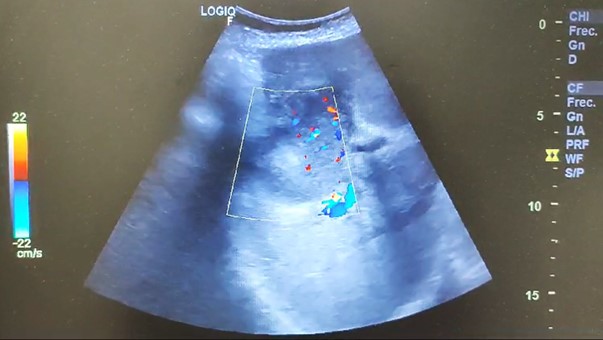

Ecografía abdominal, en la que se identifica masa hepática hipoecoica, heterogénea, de márgenes parcialmente lobulados, de 6.8 cm de diámetro, en región vesicular, con aumento de vascularización y dilatación de via biliar intrahepática. Impresiona de conglomerados adenopáticos en hilio hepático. Páncreas, bazo y riñones normales. No líquido libre intraabdominal.